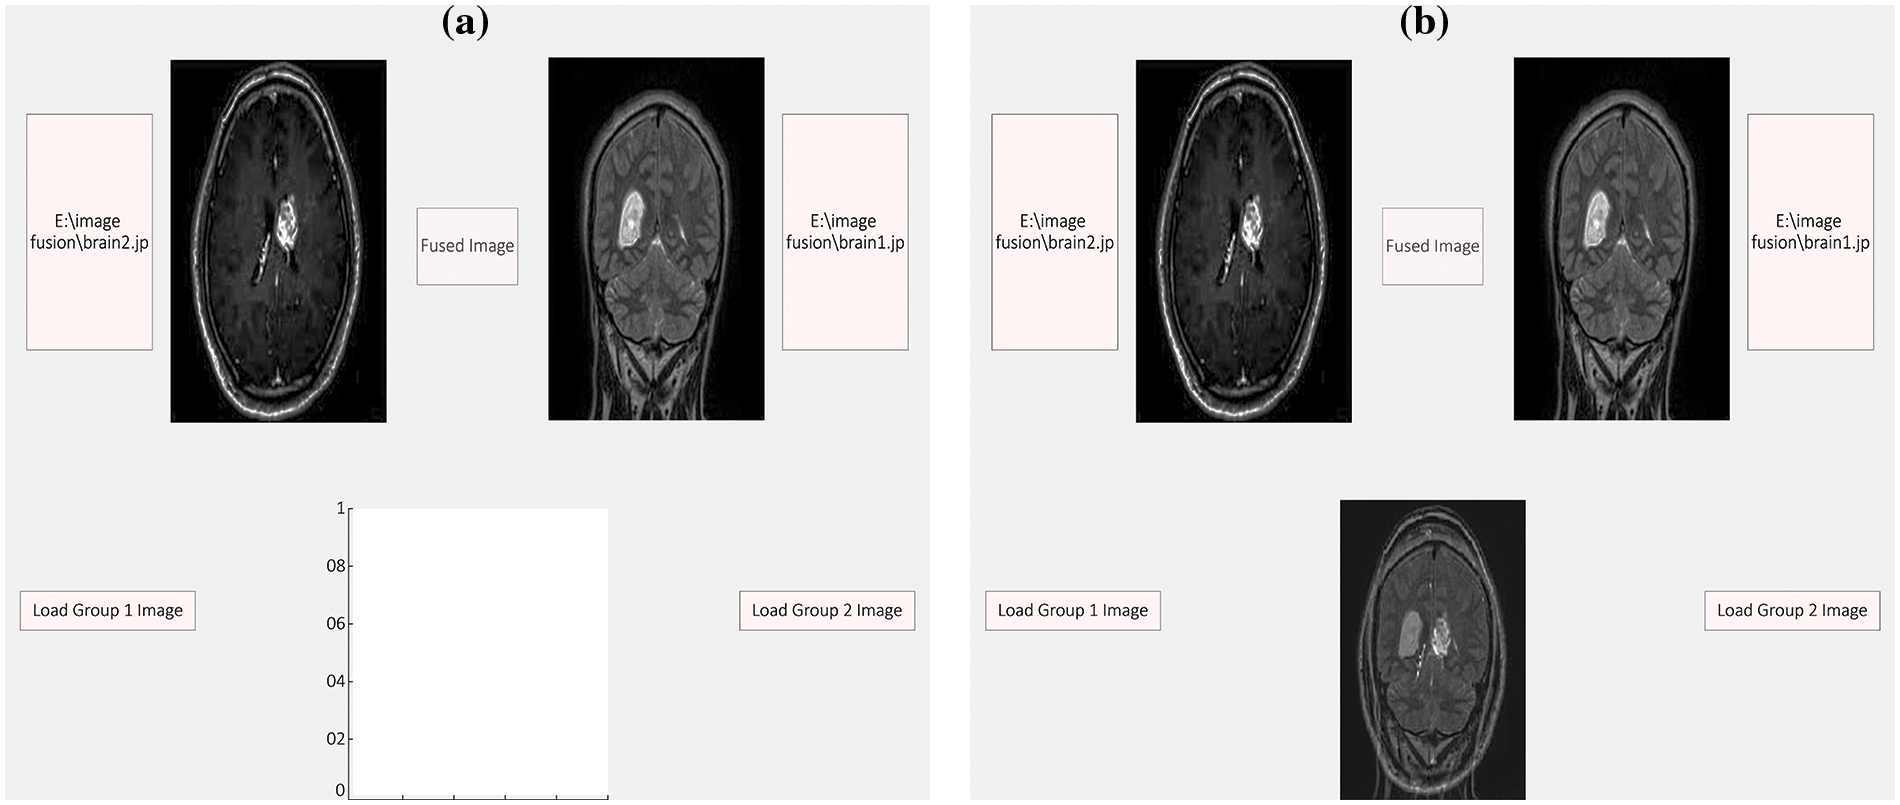

After learning the idea of DT-CWT, the following stage was to execute it. To achieve this task, this study employs the C language. The implementation of this function was done using MATLAB. The rule-based inclination combination in the Dual-Tree Complex Wavelet area has been conducted utilizing different images from a benchmark database or static images. The heartiness of the suggested combination procedure is confirmed conclusively with specific images shown in Fig. 7a, for example, multi-sensor images, multispectral remote detecting images, and clinical images, CT, MR images, Surreal images [34] using the algorithm given below:

Figure 7: The efficacy of the proposed fusion technique is definitively validated using particular images, namely: (a) Spatial gradients obtained by smoothing the average of two input images and, (b) A graphical user interface designed for image fusion

We can likewise mix ongoing images. Steps to combine the images are as follows [32]:

• We have made a graphical user interface (GUI) as appeared shown in Fig. 7b.

• We have made two textboxes to store the chosen image.

• We upload the photographs to the hub that we need to integrate. In the third Box, the combined image is shown.

• The spatial level angles of image one and image two have appeared.

• The spatial gradient is computed by applying a smoothing operation to the average vector of two merged images. Fig. 8a illustrates the fusion of the two images, while Fig. 8b the resulting combination on the third axis.